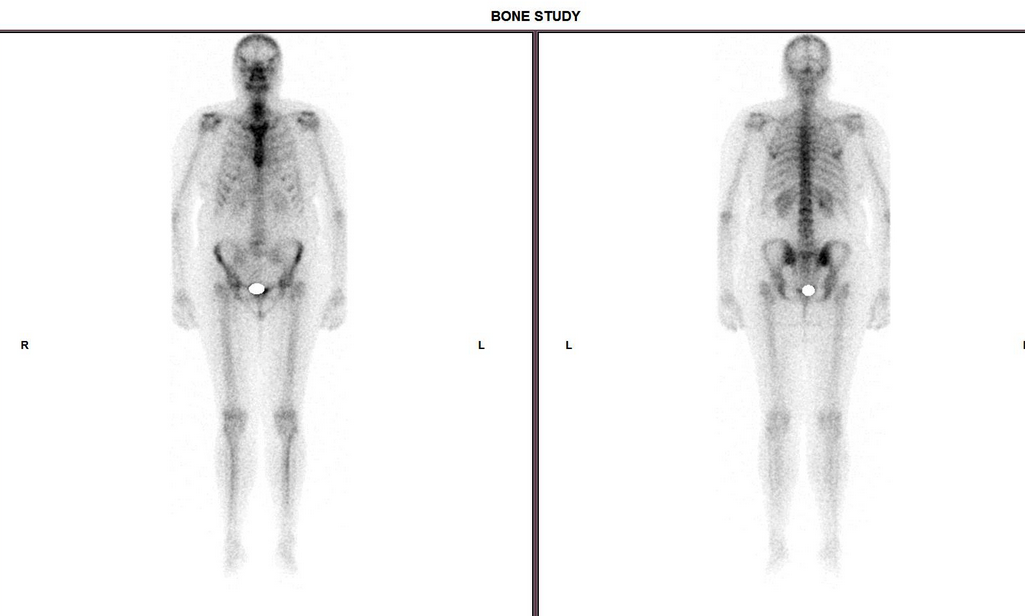

Результат только пришел, красотка правда ?

Результат:

Сцинтиграфические признаки ... вероятнее всего остеоартроз, дегенеративно-дистрофические изменения...

Убедительных данных за наличие вторичных изменений скелета не получено.

Самое главное, что наличие метастаз не выявлено. С такой наследственностью как у меня, такие диагнозы это нормально.